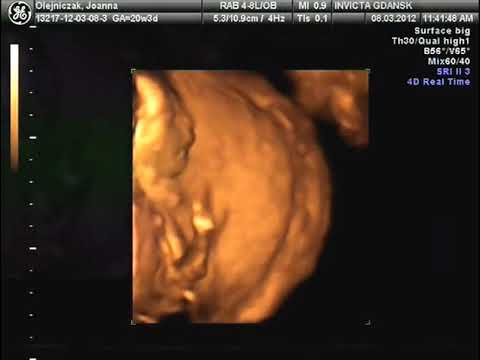

3D Ultrasound 30 Weeks Yawning Baby A New Conception 3D - YouTube

3D Ultrasound 30 weeks Yawning baby A New Conception 3D ANewConception. Subscribe Subscribed Unsubscribe. Loading Loading Working Angel Prints Ultrasound 3D/4D Ultrasounds Lafayette & Baton Rouge, Louisiana - Duration: 7:35. ... View Video

Angel Prints 3D & 4D Ultrasound - YouTube

Angel Prints 3D & 4D Ultrasound Domannic Theriot. Subscribe Subscribed Unsubscribe 1 1. Loading Loading Working Angel Prints Ultrasound 3D/4D Ultrasounds Lafayette & Baton Rouge, Louisiana - Duration: 7:35. Angel Prints Ultrasound 256,318 views. ... View Video

31 Week 4D Ultrasound Of Baby Girl - YouTube

Standard YouTube License; Music Angel Prints Ultrasound 3D/4D Ultrasounds Lafayette & Baton Rouge, Louisiana - Duration: 7:35. Angel Prints Ultrasound 259,478 views. 7:35 Baby born at 27 weeks - Charlotte's First Year - Duration: 9:33. ... View Video